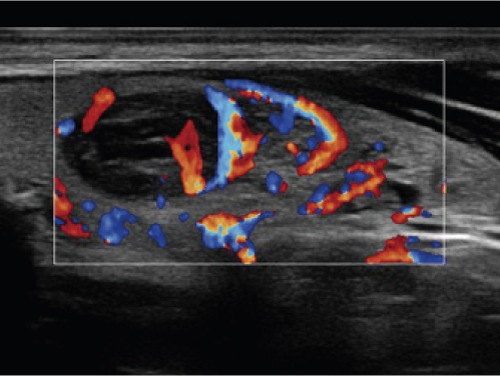

USG skóry, działające na częstotliwościach do 20 MHz, pozwala na szczegółowe obrazowanie powierzchownych warstw skóry, co jest kluczowe przy ocenie tkanki przed zabiegami modelującymi. W zależności od potrzeb klinicznych, ultrasonografia umożliwia monitorowanie głębokości tkanki tłuszczowej, oceny struktury skóry oraz określenie poziomu nawilżenia, a także precyzyjnej analizy efektów terapeutycznych w czasie rzeczywistym.